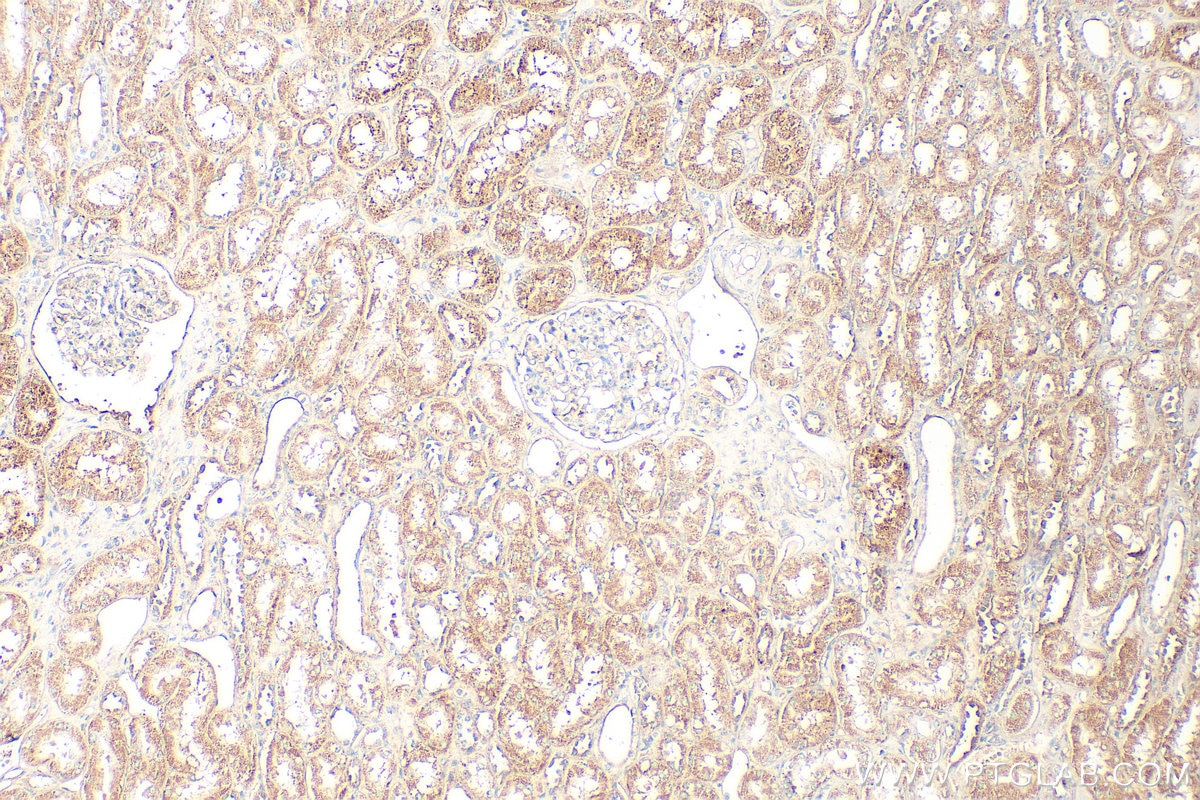

| Positive IHC detected in | human kidney tissue, mouse heart tissue Note: suggested antigen retrieval with TE buffer pH 9.0; (*) Alternatively, antigen retrieval may be performed with citrate buffer pH 6.0 |

20467-1-AP targets Spexin in IHC, IF-P, ELISA applications and shows reactivity with human, mouse samples.

Spexin (SPX), also known as neuropeptide Q, is a novel and highly conserved neuroendocrine peptide discovered through bioinformatics. Spexin and its receptors (primarily galanin receptor types 2 and 3) are widely expressed throughout the body, including the central nervous system, gastrointestinal tract, adipose tissue, kidneys, and cardiovascular system. Research indicates that Spexin is a multifunctional regulatory peptide, with its most central role being in energy homeostasis and metabolic regulation. It functions to suppress appetite, reduce body weight, and improve insulin resistance and glucose metabolism, making it a potential biomarker and therapeutic target for metabolic diseases such as obesity and type 2 diabetes. Additionally, Spexin is involved in regulating various physiological and pathological processes, including pain perception, anxiety- and depression-like behaviors, cardiovascular function, and reproductive activities.